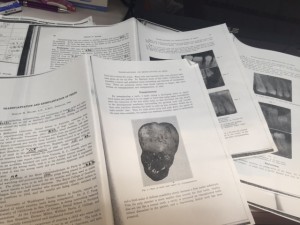

ケース1はFig2で、 『遠心根が吸収しました、抜歯の時に傷つけちゃったみたい。患者さんがWisconsinに引っ越して、今は連絡取ってない』だそうです

ケース2はFig3で、『11歳の少年に移植しましたが、歯根が出来ませんでした。このケースは歯冠が形成されてから移植しないとうまくいかない事をものがったてます』とのこと。見るも無残ですね。

ケース3はFig4で、移植後4年後のレントゲンだそうです。『P根は成長した。MB、BD根は成長が遅れを取っています』だそうです。いや、これはもうMB、BDは成長遅れてるんじゃなくて、成長しないんじゃない?笑

ケース4はFig5で、『近心に年々ポケットができてきました』とのこと。原因は書いて無いです。